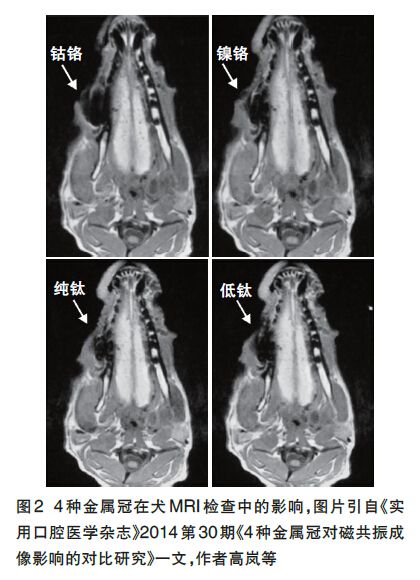

核磁共振檢查一般要盡量拆除金屬的物質,以免強大的磁場會(hui) 造成人身危害,而且一些磁性很強的金屬,會(hui) 對核磁共振的影像結果出現偽(wei) 影(也就是幹擾的陰影),可能會(hui) 影響醫生對**病情的正確認識和判斷。

但是有特殊情況,牙齒在根管治療後,通常根據需要,要做個(ge) 牙冠把牙齒整體(ti) 包起來,這樣可以起到保護根管治療後沒有牙神經的脆弱的牙齒。而牙冠的材料有金屬材質,也有貴金屬以及瓷材料,不同的材料可能對核磁共振有一定影響。

為(wei) 了不影響後期做核磁共振等檢查,目前很多醫生都會(hui) 建議選擇牙冠材質為(wei) 全瓷的,全瓷不含金屬,而且透光折光,美觀性很好,而且全瓷的強度也提升了,可以滿足前牙後牙不同的需求,所以如果有這個(ge) 擔憂的,可以直接告知醫生,可以滿足大家的需求。